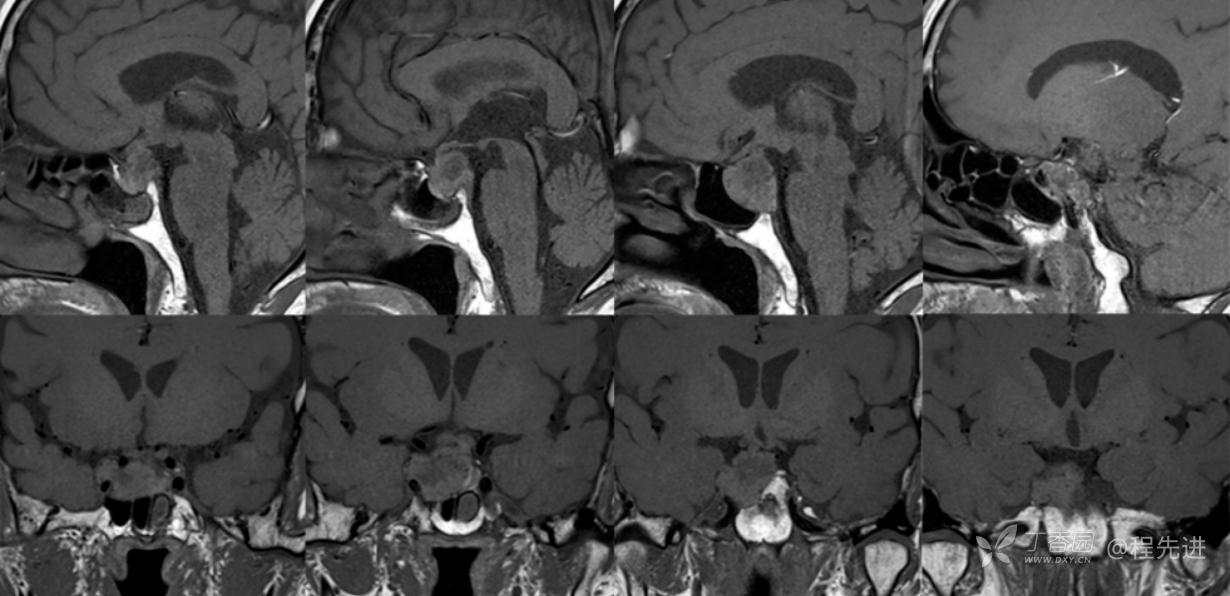

MR:

T1

组合